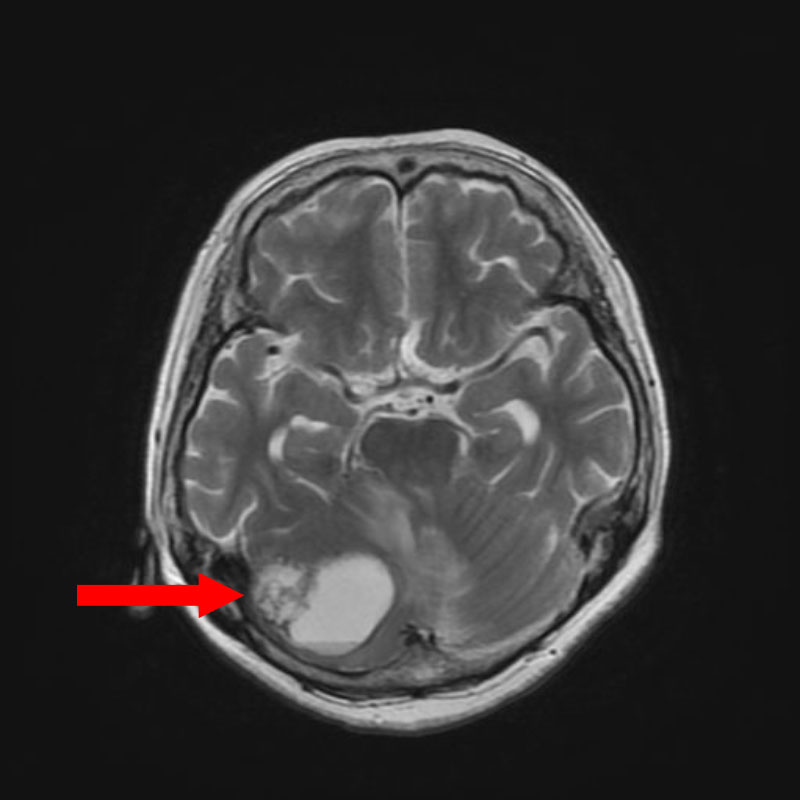

症例 '25年10月

No.

673

’25_75

'25年10月

80代

病名

術式

備考

小脳腫瘍

頭蓋内腫瘍摘出術

断層撮影

手術前

1